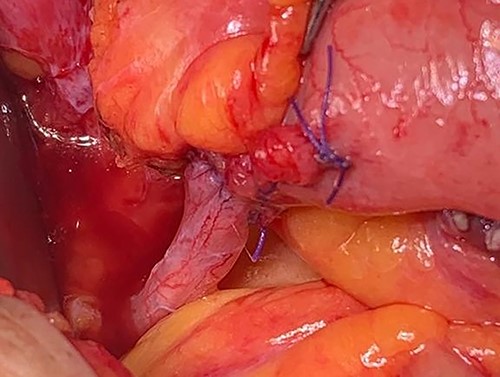

Midline incision was made and we tried to enter the Retzius space by focusing the dissection on the opposite side of the transplanted kidney. The bladder became separated from the scar tissue on the side of the graft by identifying the Cooper’s ligament as a landmark. The peritoneum was incised, and after bowel mobilization, bilateral native ureters were dissected free from their attachment and were ligated by silk 2/0 sutures. Blunt dissection was avoided in the right side to prevent injury to the graft ureter (Fig. 2). The distal ureteral margins were free of tumor in the frozen section analysis. RC was performed and maximum length of the graft ureter was preserved. Extended PLND on left side and limited PLND on right side were performed. The patient underwent ileal orthotopic neobladder reconstruction, and the graft ureter was reimplanted to ascending loop of the pouch with end-to-end anastomosis (Fig. 3).

The graft ureter was reimplanted to the ascending loop of the pouch with end-to-end anastomosis.